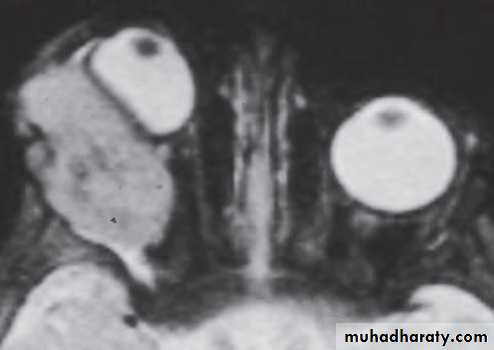

Investigation: CT and MRI show a well circumscribed oval lesion, usually within the muscle cone.